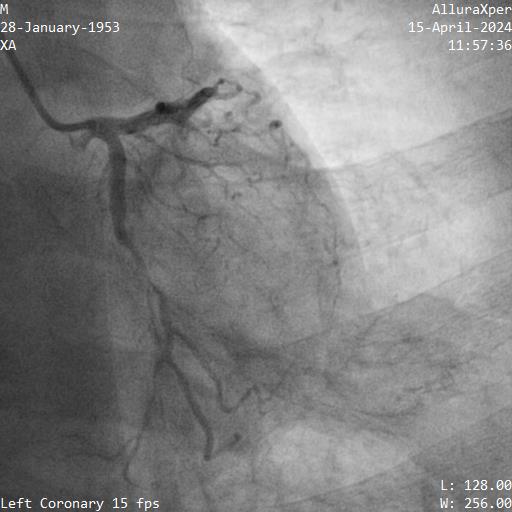

Right femoral and right radial arteries were punctured. A 7Fr EBU 3.5 guiding catheter (GC) was used to engage LMT. A 7Fr JR 4 GC was used for RCA CTO PCI. For antegrade preparation, a wire was delivered into right marginal artery. For antegrade proximal cap puncture, a Finecross microcatheter (MC) and Fielder XTR was used to wire into mid RCA CTO, but XTR fail to advance further. For retrograde approach, a CorsairPro ES (150 cm) MC, SION and SUOH 03 wire were used for LAD septal wiring but failed. A Sion Black with 90 degree tip successfully negotiate the collateral and entered PDA. The distal cap was hard to puncture. UB3 was used to puncture the distal cap and managed to cross and externalized into antegrade GC. Attempt was made to advance retrograde MC but failed at the point of PDA/PLV bifurcation.

Next plan was using retrograde UB3 to tip in antegrade MC successfully. However, the antegrade MC crossed the CTO body but failed cross PDA despite anchoring balloon at marginal artery. Next, switched to antegrade, escalated the antegrade wire to GAIA Next2 and using retrograde wire as a marker to facilitate antegrade wiring. Fortunately, the GAIA Next 2 managed to entered PLV. IVUS confirmed wire in true lumen after predilatation. The PDA was wired using CRUSADE MC to keep wire access for PDA and PLV.Distal RCA-PDA stented with everolimus eluting stent (EES) 2.5x32mm, mid RCA EES 3.5x32mm, and ostial RCA EES 4.0x24mm, post dilated NC 3.0x15mm, and 4.0x15mm balloon.

Next plan was using retrograde UB3 to tip in antegrade MC successfully. However, the antegrade MC crossed the CTO body but failed cross PDA despite anchoring balloon at marginal artery. Next, switched to antegrade, escalated the antegrade wire to GAIA Next2 and using retrograde wire as a marker to facilitate antegrade wiring. Fortunately, the GAIA Next 2 managed to entered PLV. IVUS confirmed wire in true lumen after predilatation. The PDA was wired using CRUSADE MC to keep wire access for PDA and PLV.Distal RCA-PDA stented with everolimus eluting stent (EES) 2.5x32mm, mid RCA EES 3.5x32mm, and ostial RCA EES 4.0x24mm, post dilated NC 3.0x15mm, and 4.0x15mm balloon.